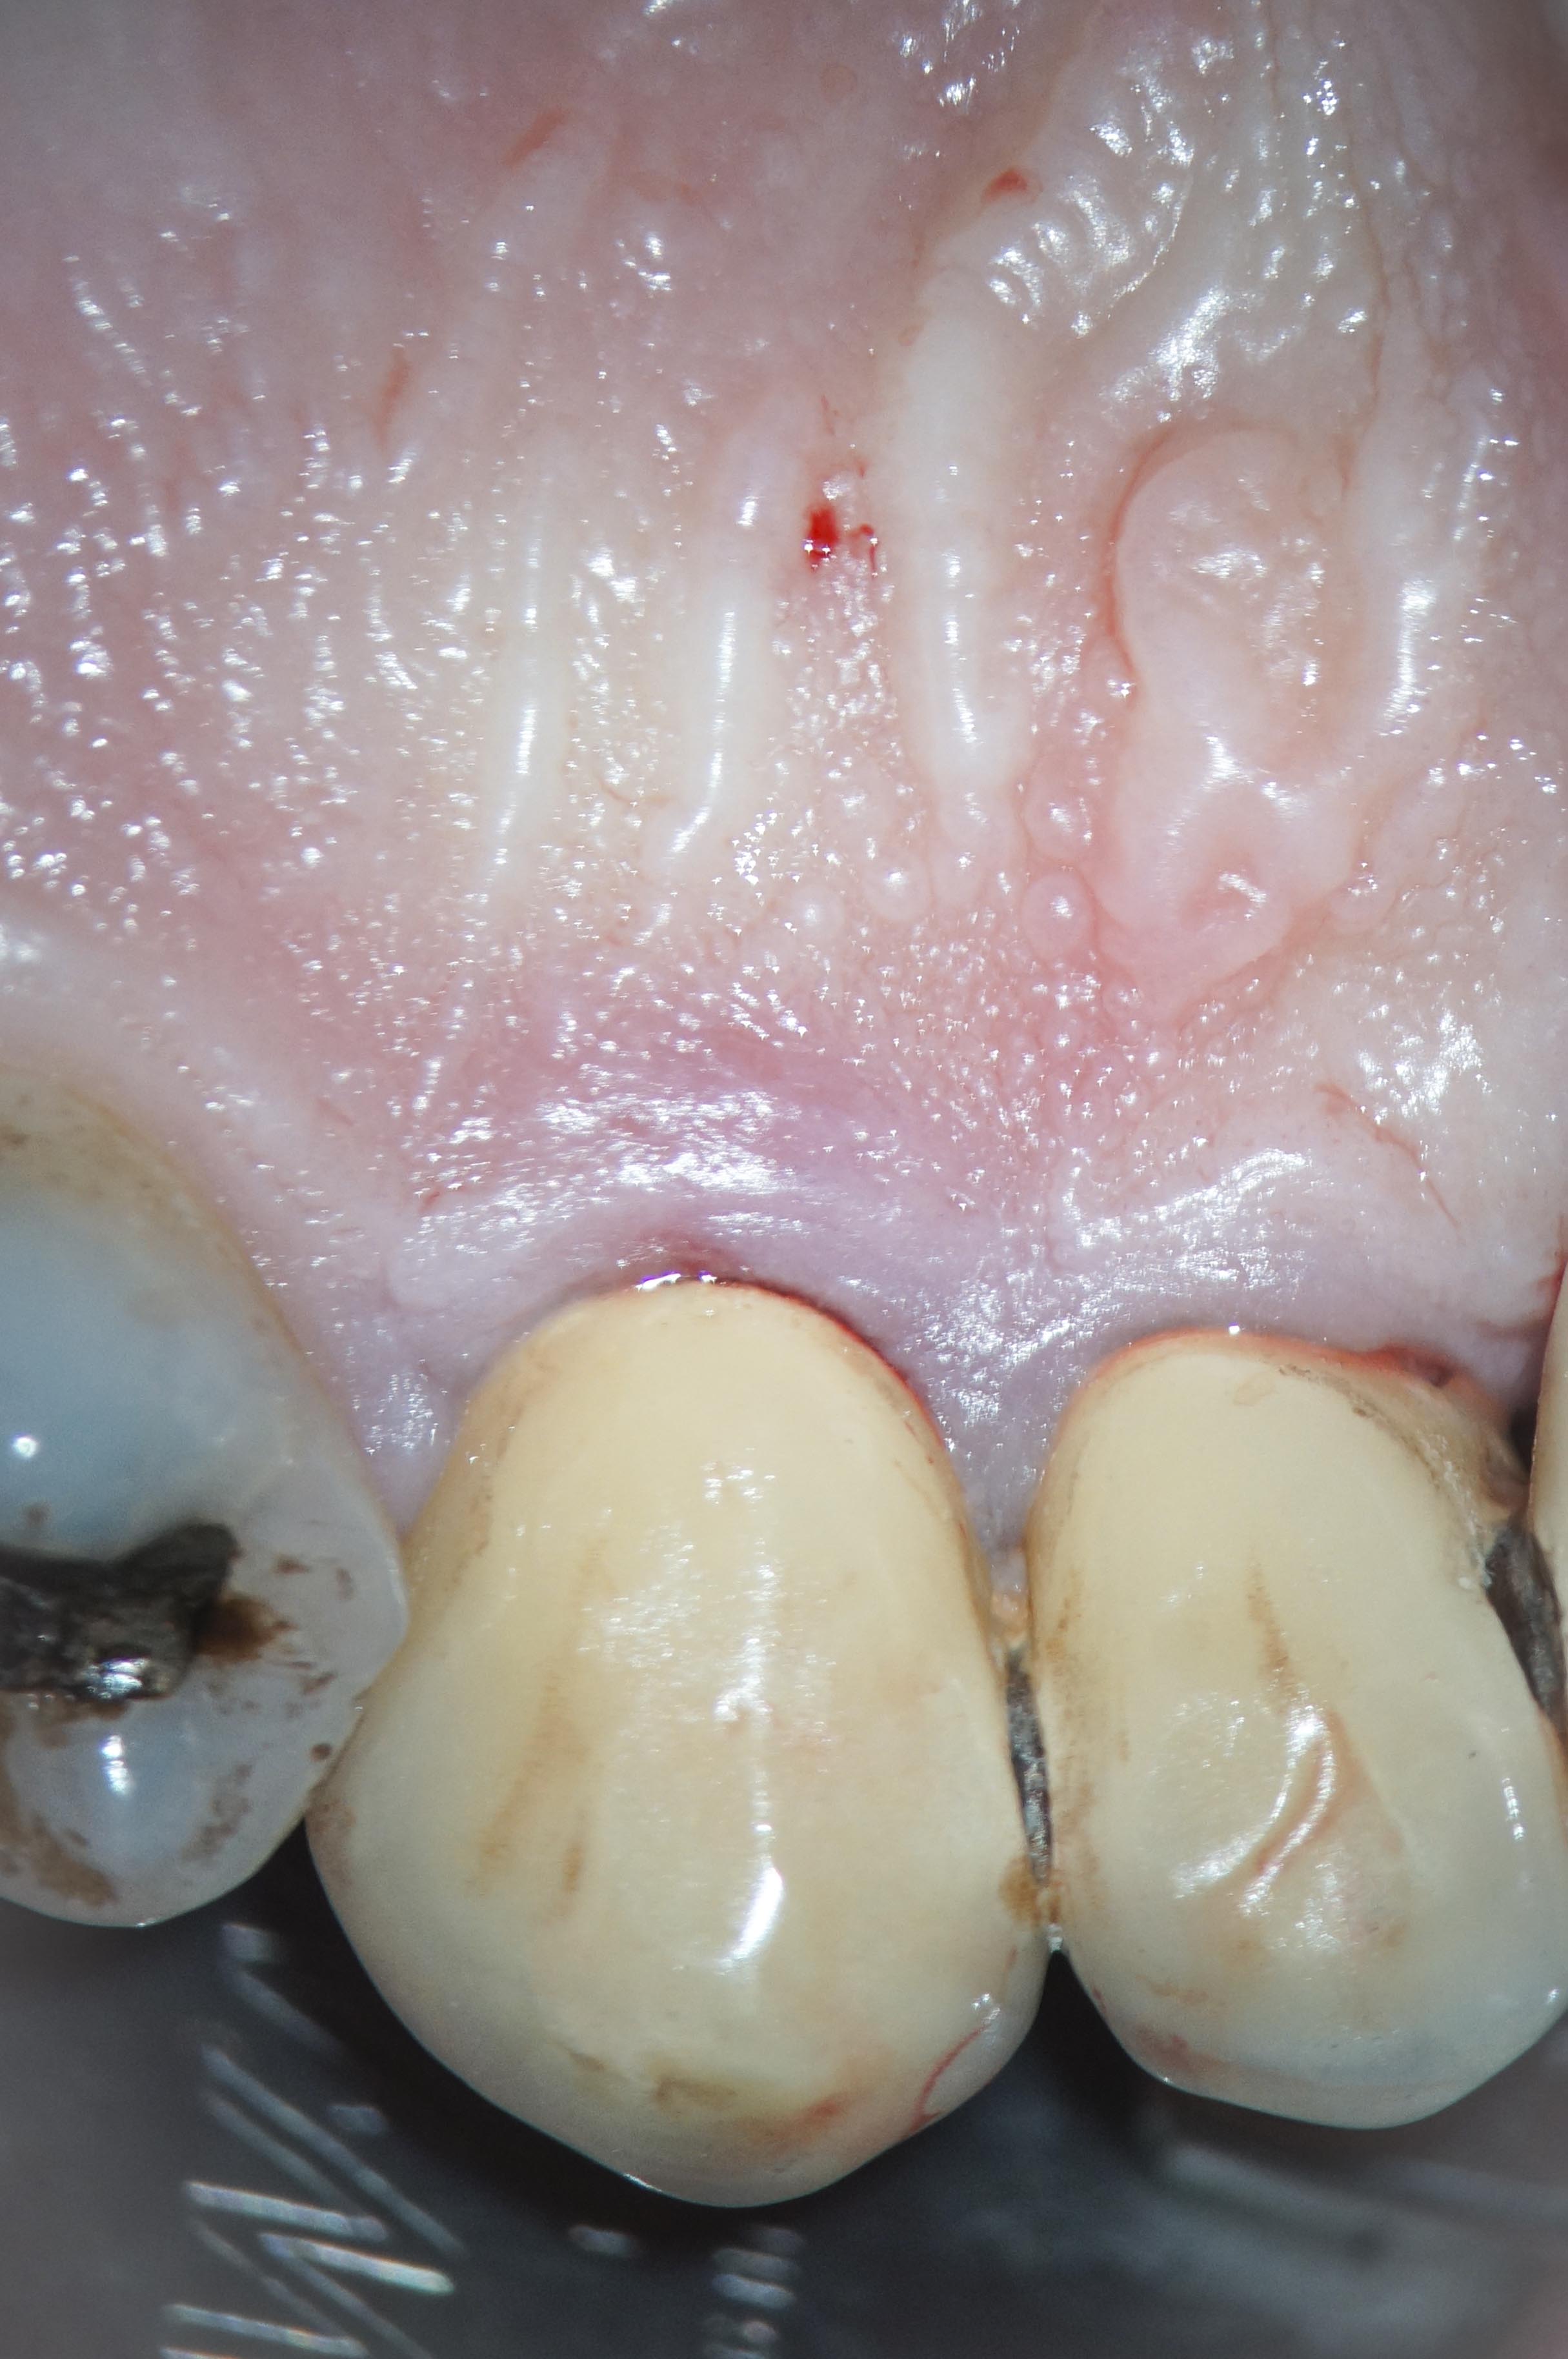

ER-1 Veröffentlicht 17. Juni 2013 am 2430 × 3656 in Was zeigt das DVT (4) – Resorptionen – Die Antworten – Fall 1